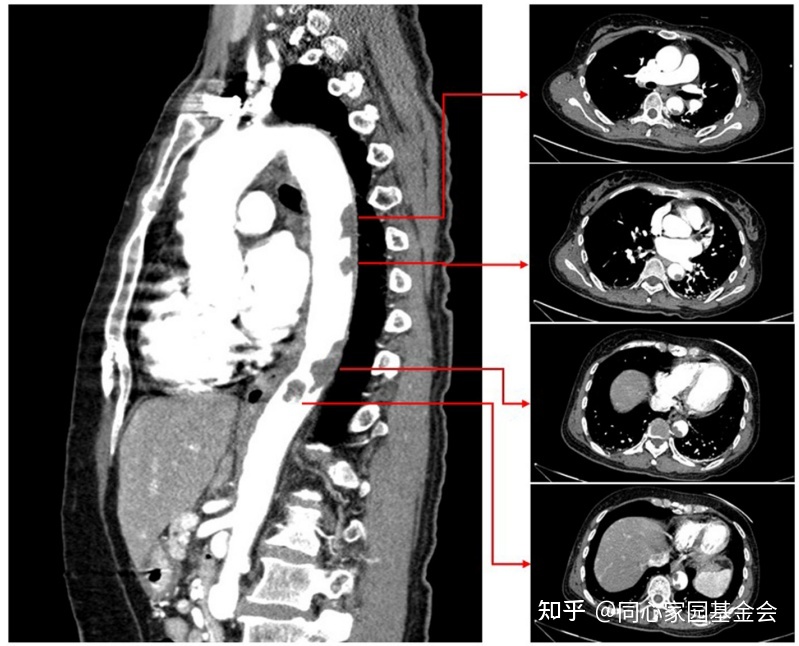

CTA显示降主动脉有大量附壁血栓(图3)。开始给予依诺肝素(8000 IU/天)。

图3:CTA显示巨大的降主动脉壁血栓。

抗凝治疗10天后,CTA复查显示主动脉壁血栓明显变小(图4)。

图4:复查CTA 显示主动脉壁血栓显著变小。